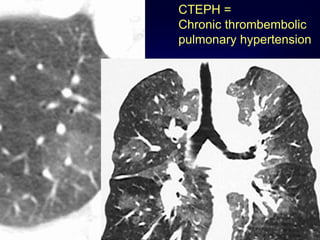

Mosaic Perfusion

Chronic pulmonary embolism

LOOK FOR

Pulmonary hypertension

idiopathic, cardiac disease, pulmonary

disease

CTEPH =

Chronic thrombembolic